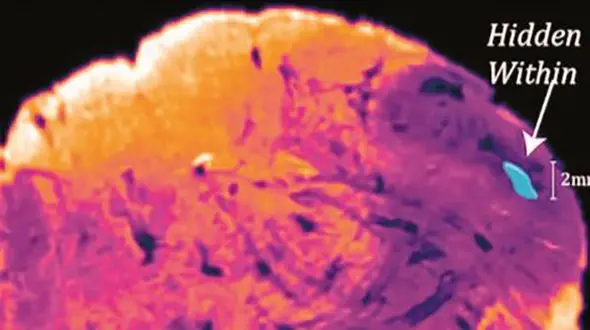

رکنا: دانشمندان بخش جدیدی در مغز انسان کشف کردهاند که عملکرد آن هنوز دقیقا مشخص نیست.